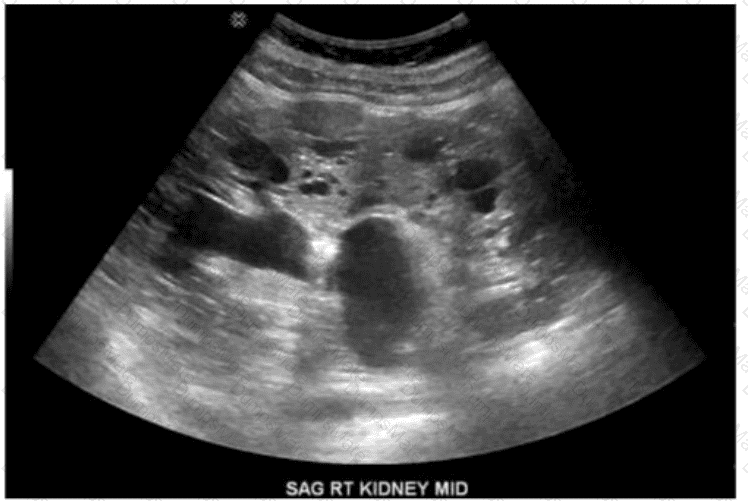

Which renal anomaly is demonstrated on this image?

AB-Abdomen Question 24

Options:

A.

Duplicated collecting system

B.

Crossed renal ectopia

C.

Horseshoe kidney

D.

Pelvic kidney